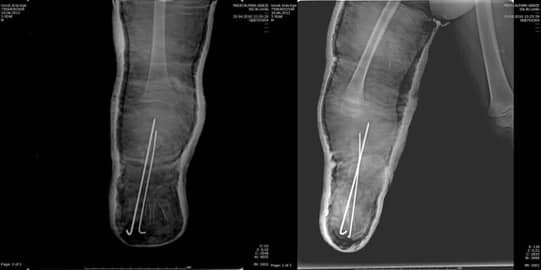

Операцията протече със запазване на пателарния сухожил и отстраняване на клиновидно-метатарзалната връзка, която притискаше кожата. По време на измерванията беше извършена отворена клиновидна остеотомия за корекция на деформацията в две равнини поради наличието на бизагитална деформация. Отстранената клиновидно-метатарзална връзка беше поставена в празната остеотомична зона за сливане, а фиксацията беше осъществена с плоча и винтове (Фиг. 9 А, В, С, D, E, F)

Фиг. 9

А: Отворена клиновидна остеотомия

B: Отстранен автотрансплантат от 4-ти метатарзал

C: Фиксация с плоча и винтове

D: Следоперативен антеропостериорен изглед

E: Следоперативен латерален изглед

F: Следоперативен кос изглед

В края на втория следоперативен месец пациентът нямаше болка и рентгеновото изследване показа сливане на костта на мястото на остеотомията (Фиг. 10 А, В).

Фиг. 10. След 2 месеца рентгеновото изследване показва сливане на костта на:

А. Латерален изглед

В. Антеропостериорен изглед